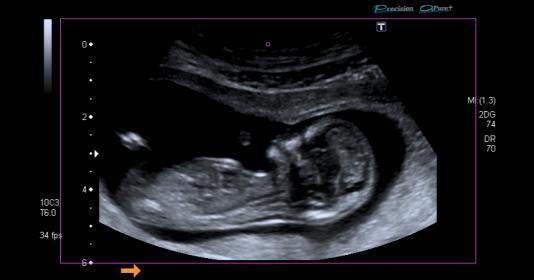

Boy lean from first pic. Not sure though. Any more pics?

I am torn 50/50 for me....maybe a slight slight lean girl.